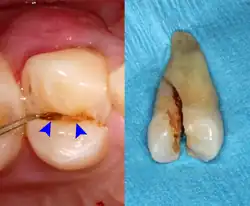

Pericoronitis is inflammation of the soft tissues surrounding the crown of a partially erupted tooth.[25] The lower wisdom tooth is the last tooth to erupt into the mouth, and is, therefore, more frequently impacted, or stuck, against the other teeth. This leaves the tooth partially erupted into the mouth, and there frequently is a flap of gum (an operculum), overlying the tooth. Bacteria and food debris accumulate beneath the operculum, which is an area that is difficult to keep clean because it is hidden and far back in the mouth. The opposing upper wisdom tooth also tends to have sharp cusps and over-erupt because it has no opposing tooth to bite into, and instead traumatizes the operculum further. Periodontitis and dental caries may develop on either the third or second molars, and chronic inflammation develops in the soft tissues. Chronic pericoronitis may not cause any pain, but an acute pericoronitis episode is often associated with pericoronal abscess formation. Typical signs and symptoms of a pericoronal abscess include severe, throbbing pain, which may radiate to adjacent areas in the head and neck,[21][26]: 122 redness, swelling and tenderness of the gum over the tooth.[27]: 220–222 There may be trismus (difficulty opening the mouth),[27]: 220–222 facial swelling, and rubor (flushing) of the cheek that overlies the angle of the jaw.[21][26]: 122 Persons typically develop pericoronitis in their late teens and early 20s,[28]: 6 as this is the age that the wisdom teeth are erupting. Treatment for acute conditions includes cleaning the area under the operculum with an antiseptic solution, painkillers, and antibiotics if indicated. After the acute episode has been controlled, the definitive treatment is usually by tooth extraction or, less commonly, the soft tissue is removed (operculectomy). If the tooth is kept, good oral hygiene is required to keep the area free of debris to prevent recurrence of the infection.[21]: 440–441

Sometimes the symptoms reported in the history are misleading and point the examiner to the wrong area of the mouth. For instance, sometimes people may mistake pain from pulpitis in a lower tooth as pain in the upper teeth, and vice versa. In other instances, the apparent examination findings may be misleading and lead to the wrong diagnosis and wrong treatment. Pus from a pericoronal abscess associated with a lower third molar may drain along the submucosal plane and discharge as a parulis over the roots of the teeth towards the front of the mouth (a "migratory abscess"). Another example is decay of the tooth root which is hidden from view below the gumline, giving the casual appearance of a sound tooth if careful periodontal examination is not carried out.